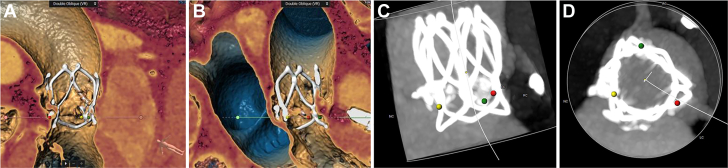

Figure 4.

Computed Tomography Scan at 6-Month Follow-Up

(A to D) Morphology of the prosthesis and the relationship with surrounding tissues.

Postprocedural treatments included warfarin, diuretics, antihypertensives, and beta-blockers. Anticoagulation therapy with excellent biocompatibility is not essential for this novel valve. However, the patient had indications for anticoagulation therapy because of atrial fibrillation. After discharge, the patient was administered rivaroxaban. Follow-up transesophageal echocardiography indicated that the valve worked well (Table 1, Video 6). At 6-month follow-up, CT showed that the morphology of the prosthesis was normal (Figure 4). NYHA functional classification improved from IV to II. Six-minute walking distance increased to 430 m. No nocturnal paroxysmal dyspnea, shortness of breath, or syncope occurred.